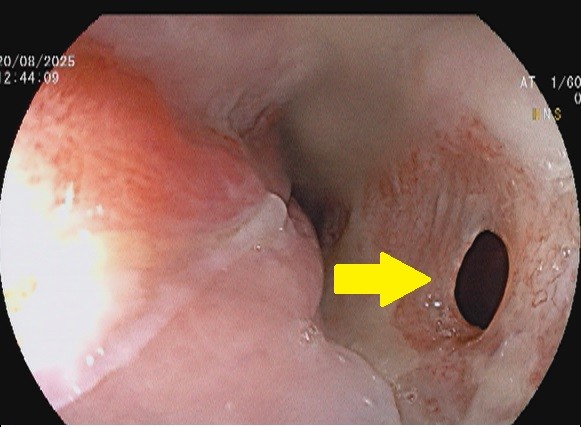

Esophageal cancer, a highly aggressive malignancy, frequently presents with advanced-stage dysphagia, significantly impacting patient quality of life [1]. While surgical resection offers the best chance for cure in early stages, many patients are diagnosed with unresectable or metastatic disease, necessitating palliative interventions to alleviate symptoms. In such instances, endoscopic palliation, particularly with the deployment of self-expanding metal stents, plays a crucial role in restoring luminal patency and improving oral intake [2]. This case details the successful application of an esophageal self–expanding metal stent for palliation of unresectable esophageal cancer, highlighting its efficacy and safety profile in a real-world clinical scenario. This intervention is often considered first–line therapy for such management given its efficacy in rapidly restoring esophageal patency and improving patient's nutritional intake [3]. We present a case of 52-year-old male with biopsy proven case of squamous cell carcinoma of esophagus with history dysphagia and recurrent cough especially after food intake. The patient was evaluated thoroughly and esophagogastroduodenoscopy was done which was suggestive of ulcerated growth with narrowing from 20 cm to 27 cm from incisors, and a small circular defect was seen at around 24 cm suggestive of tracheo–esophageal fistula (Figure 1).

Figure 1. Endoscopic image showing ulcerated growth causing narrowing of esophageal lumen along with a small circular defect suggestive of tracheo-esophageal fistula (yellow solid arrow).